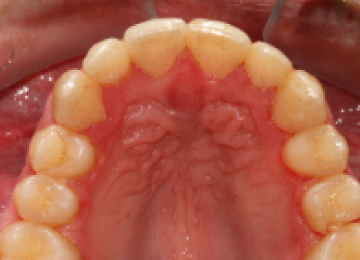

Установка брекетов подросткам: фото До и После

Закреплением результата после снятия брекет-систем, как правило является использование ретенционного аппарата в виде пластинок или капп, а также в виде маленькой металлической дуги, закрепляемой с внутренней стороны зубов. Важно понимать, что чем раньше начато лечение по исправлению прикуса, тем быстрее оно проходит, с меньшими сложностями и более предсказуемым результатом. Кстати, оплата распределяется частями, по каждому этапу, так что не стоит пугаться, когда полная стоимость исправления прикуса выглядит внушительно.